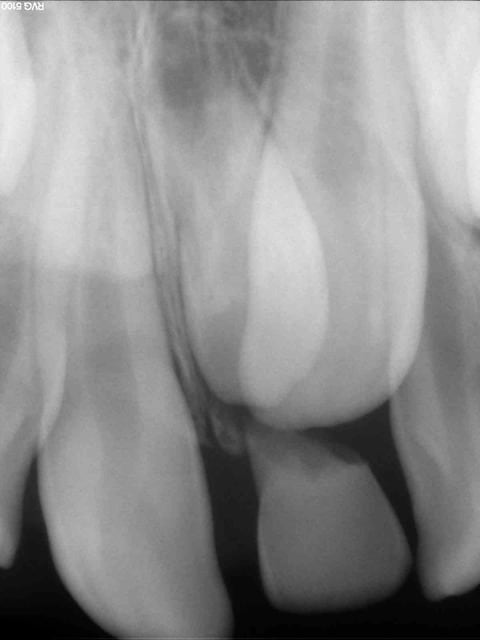

Besoin d'avis sur la prise en charge pour cette petite fille de 10 ans .

Sa 61 est toujours présente, rhisalysée. C'est au dessus que ça bloque, à la radio on peut voir une sorte de mésiodens qui bloquerai la 21.

Vos avis ? Stomato puis ortho ou l'inverse ?

à 10 ans, 21 pas en place, c'est sûr, il faut déjà opérer retirer 61 et le mesiodens, l'ortho pourra être consulté dans la foulée car il y a un encombrement important dans le secteur antérieur

Une 3D pour faire un diagnostic précis... et de longues explications pour les parents... tout cela avant d'extraire cette 61....

Plus que le mesiodense c'est le rapport des canines avec les latérale qui m’inquiète

ça change beaucoup pour le chirurgien qui va l'enlever!!!

Mais la 3D va nous permettre de préciser le rapport anatomique avec les dents définitives, la position des canines et donc le ou les plans de traitement possible.

oui, ce qui est intéressant ce sont les rapports des 13 et 23 avec les apex des 12 et 22 qui pour l'instant semblent encore intact.